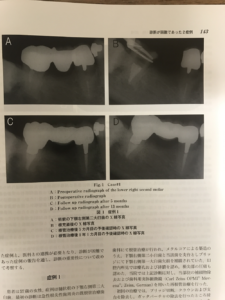

3.最初の症例は根の先端2ミリが直角に曲がっていて、そこにリーマーという針のようなたいへん細い手用器具が折れて食い込んでいるために、骨が溶け歯茎が腫れていたためにマイクロスコープ(顕微鏡)と超音波器具を使って取り出しその後、根管(根の中)をきれいにして根充(根の中を詰める)したことによって歯茎の腫れが治り溶けた骨も再生されました。

最近では破折リーマーの除去はしばしば海外の学会では発表されるのですがこの場所にこのように食い込んでいるリーマーを除去するのは危険すぎ不可能と思われているので、私が発表するとだいたいスタンディングオベーションになります。